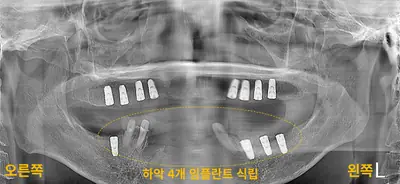

치과 치료를 두려워하는 분들을 위해, 진정요법을 활용한 사례를 소개합니다. 부산에 거주하던 60대 여성 환자가 치아가 많이 손상되어 임플란트와 브릿지 치료를 받았는데, 병원 트라우마와 공포로 어려움이 있었어요. 의식하 진정요법을 통해 깊은 낮잠 같은 상태에서 안전하게 치료를 받았고, 수술 과정도 성공적이었어요. 이 방법은 전신마취보다 안전하고, 환자도 큰 두려움 없이 치료를 마칠 수 있어요. 치과 공포증이 심한 분들도 전문가와 상담 후 진정요법을 고려해보시면 좋겠습니다.